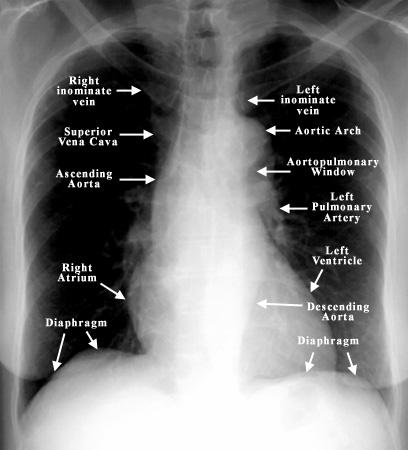

You have completed this module. Labeled chest radiographs teaching radiologic anatomy with a level of detail appropriate for medical students. Chest radiographs are the most common film taken in medicine. Evaluation of a chest radiograph may appear to be simple, but is in fact a complex task requiring careful observation, sound understanding of chest anatomy, and knowledge of the principles of physiology and pathology. Air spaces normally seen in.

Recognizing normal chest anatomy and a technically adequate chest radiograph. Abcde aproach the anatomy of the heart can appear artificially larger due to this image orientation. Submitted 2 years ago by gmdmd. You have completed this module. The interpretation of a chest film requires the understanding of basic principles. Learn vocabulary terms and more with flashcards games a. There are also important structures that are obscured or become visible. Common symptoms that can be diagnosed using chest. Conclusion of living anatomy of the chest congratulations! Clinicalchest xray anatomy labeled clinical (i.redd.it). Look for lung and pleural pathology. Evaluation of a chest radiograph may appear to be simple, but is in fact a complex task requiring careful observation, sound understanding of chest anatomy, and knowledge of the principles of physiology and pathology. Xray is a type of radiography and most widely used investigation.

In this article we will focus on: They contain air and so are of lower density (blacker) than the surrounding soft tissues. Abcde aproach the anatomy of the heart can appear artificially larger due to this image orientation. Air spaces normally seen in. Each of these anatomical structures should be viewed using a systematic approach. Many clinical conditions can be evaluated by this simple radiology test. This imaging method can also check how a patient is responding to specific treatments. A collection of anatomy notes covering the key anatomy concepts that medical students need to learn. You have completed this module. In fact every radiologst should be an expert in chest film reading. It first appears too complicated to read the chest xrays because we barely know what. Submitted 2 years ago by gmdmd. It is almost always the first imaging study ordered to evaluate for pathologies of the thorax, although further diagnostic imaging, laboratory tests.

Each of these anatomical structures should be viewed using a systematic approach. They contain air and so are of lower density (blacker) than the surrounding soft tissues. Conclusion of living anatomy of the chest congratulations! Chest radiographs are the most common film taken in medicine. Submitted 2 years ago by gmdmd. Common symptoms that can be diagnosed using chest. Recognizing normal chest anatomy and a technically adequate chest radiograph. Evaluation of a chest radiograph may appear to be simple, but is in fact a complex task requiring careful observation, sound understanding of chest anatomy, and knowledge of the principles of physiology and pathology.